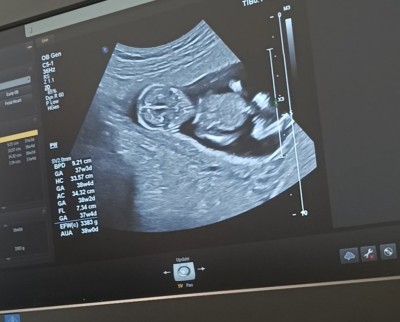

11 haftalık ve 13+5 haftalık ultrason görüntülerimiz doktor cinsiyette emin olamadi önce erkek sonra kız dedi ama sizin tahminleriniz neler?

Gebelik haftası 13+5